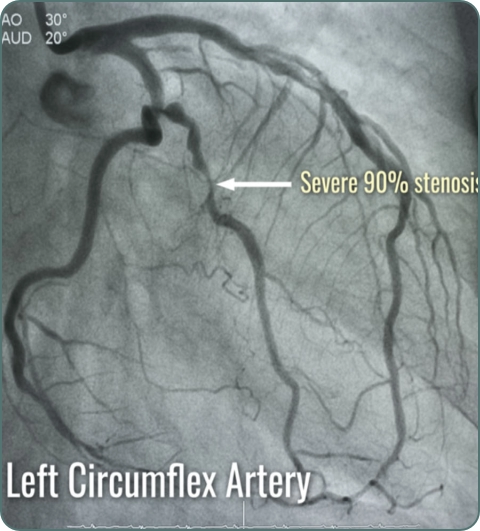

Coronary Angiography

X-ray imaging of coronary arteries using contrast dye. Gold standard for diagnosing coronary artery disease and planning interventions.